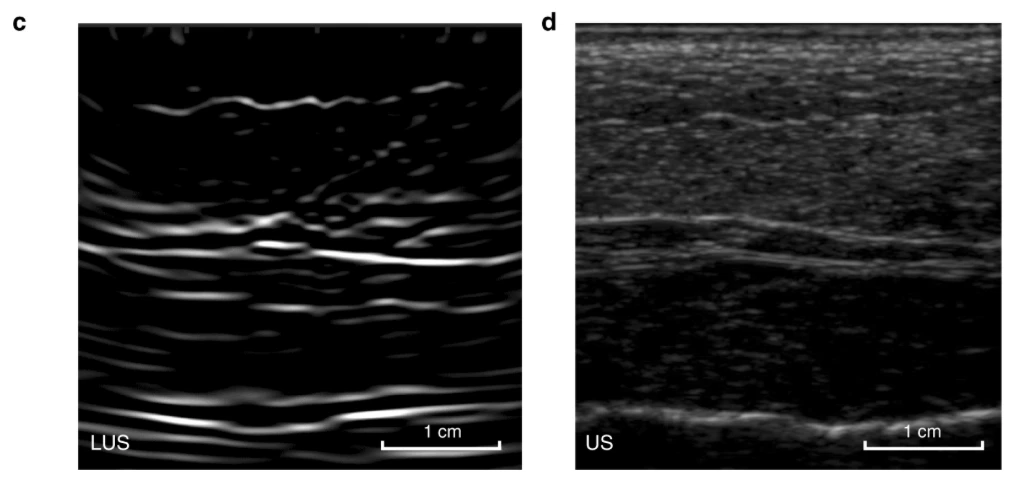

Early test image of gelatin mold with steel rod. Laser ultrasound on the left, traditional ultrasound on the right

In the new study, the researchers demonstrate the successful development of this novel laser ultrasound technique, from initial tests on a gelatin mold resembling human skin, to excised animal tissue. The study ultimately demonstrates the method’s efficacy in human volunteers, presenting the first non-contact laser ultrasound images of a human forearm.